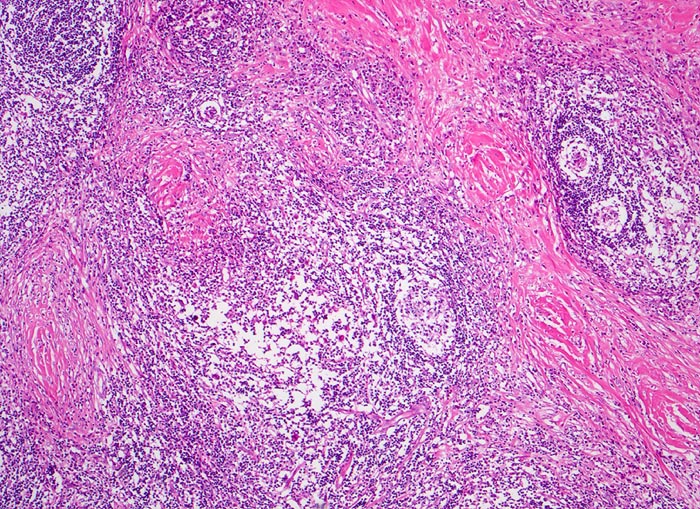

Histologisch charakteristisch für diesen Subtyp sind Sklerose, noduläres Wachstumsmuster und Lakunarzellen. Bei der nodulären Sklerose können Grad I und Grad II (15-25%) Lymphome unterschieden werden; unter modernen Therapiekonzepten allerdings ohne prognostische Bedeutung

• Zerstörung der Lymphknotenarchitektur.

• Von breiten Bindegewebssträngen abgegrenzte Knoten.

• Die Knoten bestehen vorwiegend aus einem Mischzellinfiltrat reaktiver Zellen: Lymphozyten, Histiozyten, eosinophile Granulozyten und Plasmazellen.